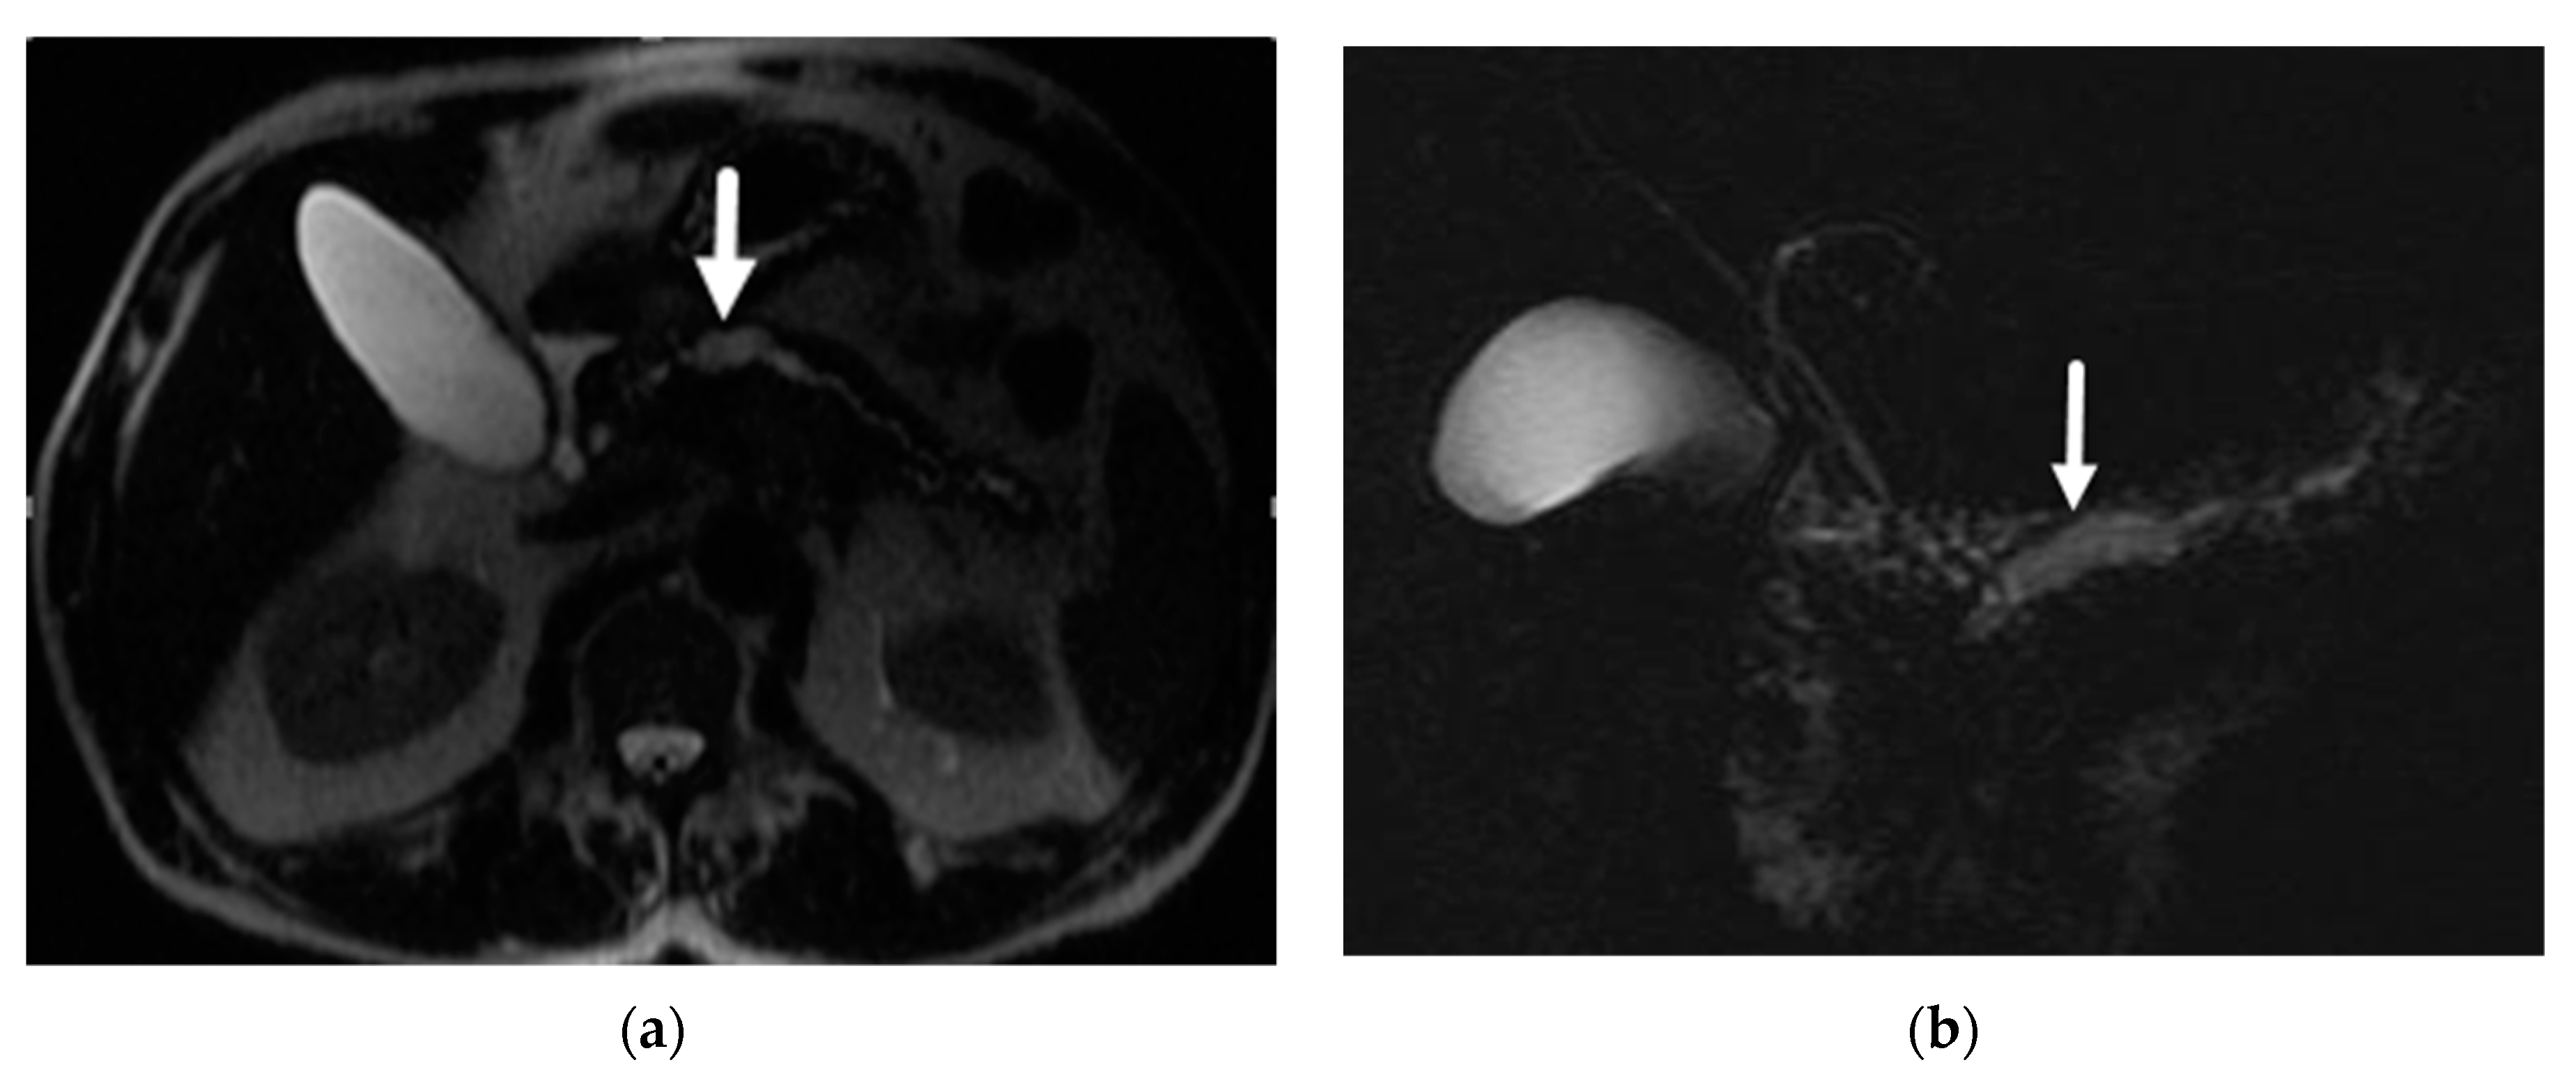

- Mamone, G.; Barresi, L.; Tropea, A.; Di Piazza, A.; Miraglia, R. MRI of mucinous pancreatic cystic lesions: A new updated morphological approach for the differential diagnosis. Updates Surg. 2020, 72, 617–637. [Google Scholar] [CrossRef] [PubMed]

- Garces-Descovich, A.; Beker, K.; Castillo-Angeles, M.; Brook, A.; Resnick, E.; Shinagare, S.; Najarian, R.M.; Mortele, K.J. Mucinous cystic neoplasms of the pancreas: High-resolution cross-sectional imaging features with clinico-pathologic correlation. Abdom. Radiol. 2018, 43, 1413–1422. [Google Scholar] [CrossRef]